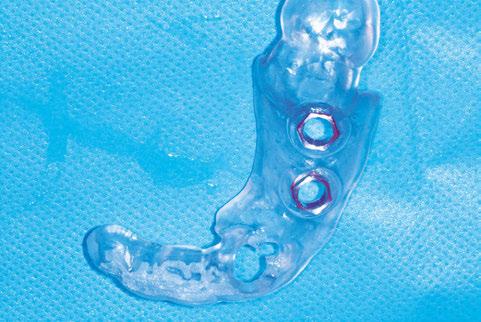

–Planificación de cirugía guiada de implantes con sistema de guía quirúrgica sin anillas metálicas: a propósito de un caso clínico, por el Dr. Antonio García Sanz y cols. [64]